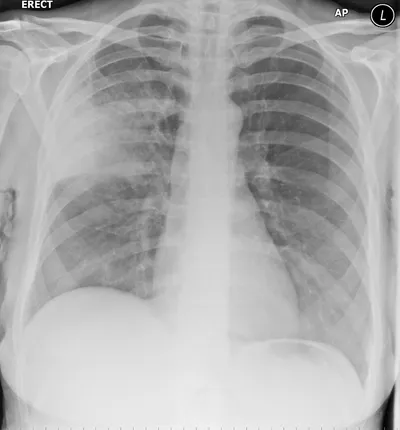

Avascular Necrosis right femoral head

XRAYAVNAvascular Necrosis+1

4/23/2026